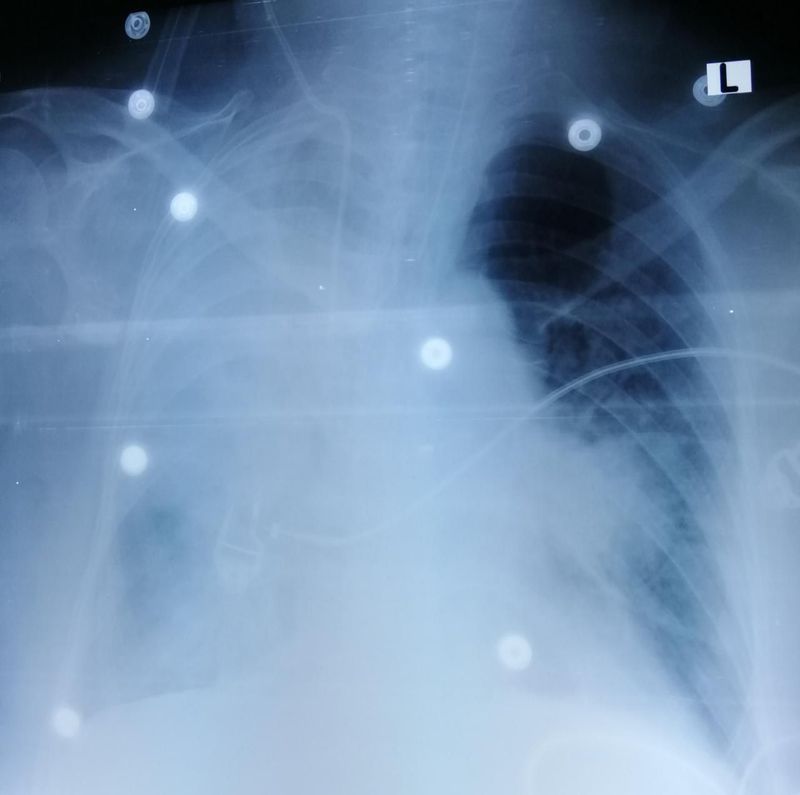

CXR of a 54 year old female, IHD, DM, Gastroenteritis with Acute Kidney Injury. Normal chest X-ray 1 day ago. Now presentating with SOB.